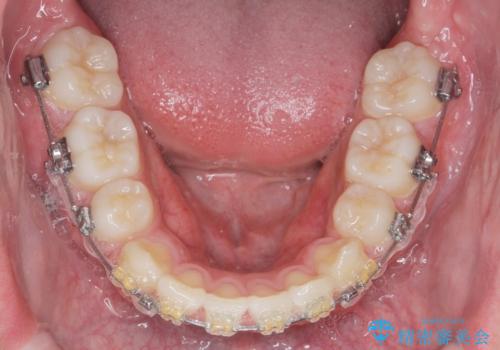

- 前歯のがたつきが原因で歯ブラシしづらい、見た目を改善したい!と矯正治療を希望され来院されました。

スペースの不足が見られるため、小臼歯の4本抜歯を行いマルチブラケットを用いた矯正治療を計画します。

噛み締めが強く、治療に時間がかかりましたが矯正治療の仕上がりに満足いただくことができました。